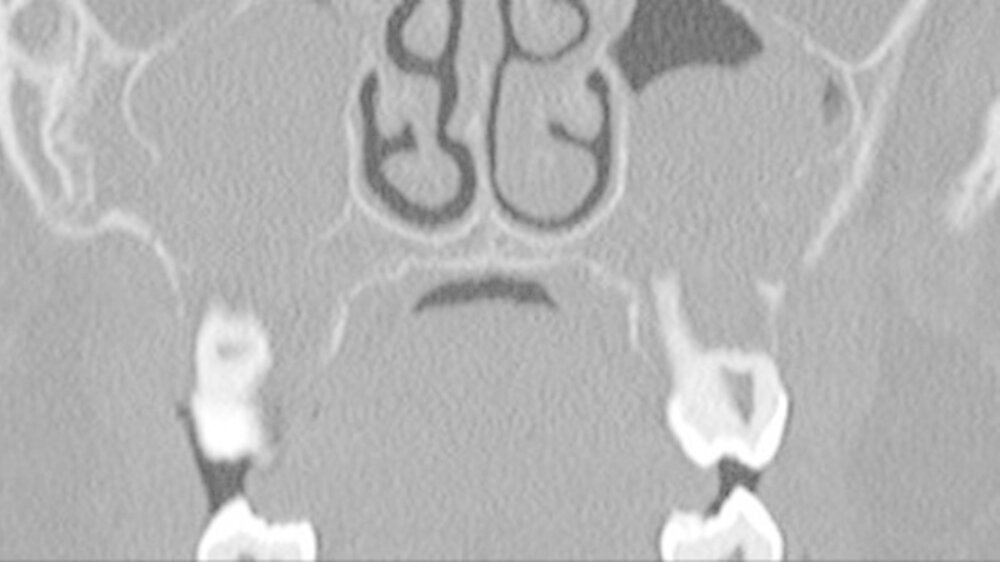

Da die konventionelle Röntgenuntersuchung keinen wegweisenden Befund zeigte, wurde die bildgebende Diagnostik um eine Dünnschicht-Computertomografie (HR-CT) des Mittelgesichts, eine Magnetresonanztomografie (MRT) des Kopf-Hals-Bereichs und eine Halssonografie erweitert.

In der HR-CT zeigten sich Arrosionen am Oberkiefer und Kieferhöhlenboden sowie eine irreguläre Knochenbinnenstruktur mit Rarefizierung der Kochentrabekel und Demineralisation im Mittelgesichtsbereich, weiterhin eine Verschattung der Kieferhöhlen beidseits (Abbildungen 2 und 3).